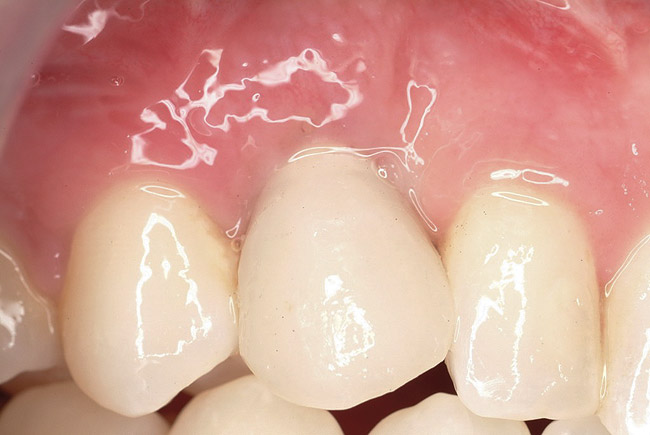

Ten weeks after implant insertion, the patient presented to begin soft-tissue contouring via a fixed, provisional crown (Figure 10). Deliberate under-contouring of the cervical portion of the temporary restoration was performed to avoid unwanted mucosal recession and possible esthetic complications (Figure 11 and Figure 12).

Figure 10   Soft-tissue contouring 10 weeks after implant insertion.

Figure 10

Figure 11  Temporary restoration.

Figure 11